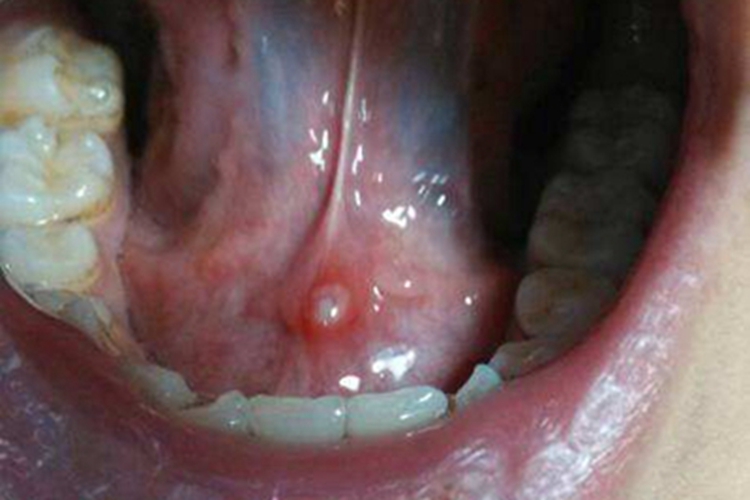

舌癌可发生在部分患者的舌根,表现为黏膜表面有一个疱疹,形状为圆形,周围有红晕,向上突起,高于皮肤表面,疱疹表面光滑,紧张发亮,破溃后往往形成较大溃疡。患者正常说话、进食可受影响。